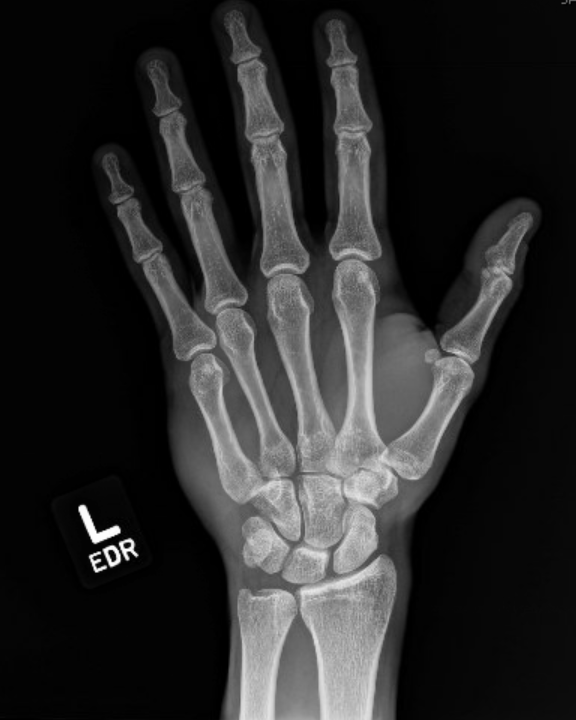

The patient punched a wall in an episode of frustration with his left hand and has pain and swelling over the ulnar aspect of his hand and wrist. What is the diagnosis?